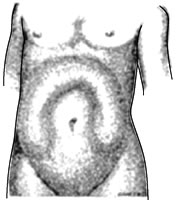

図2 イレウスによる腹部の膨満

ところが腸管が閉塞する(ふさがる)と消化途中の食べ物だけでなく、消化液も再吸収されずに貯まってしまい、腸がふくれてきます。そのため、腹痛、おう 吐、便が出ない、ガス(おなら)が出ない、お腹がはるなどの症状が出ます。